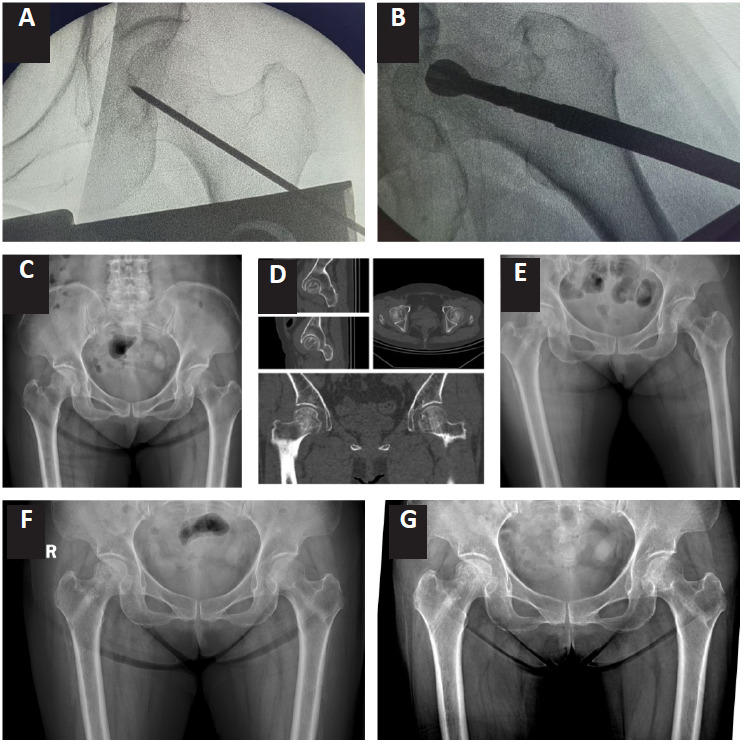

股骨头缺血性坏死是一种由血液供应中断引起的疾病,可导致缺血和骨组织坏死。核心减压(CD)通过减压恢复血液供应,而高压氧(HBO)增强组织氧合并促进骨修复。两者联合使用可在改善血液供应、促进骨愈合、抑制疾病进展等方面相辅相成,达到更好的治疗效果。为了评估和比较HBO和/或CD治疗轻中度股骨头缺血性坏死的疗效,我们对中国沈阳医科大学附属中心医院2017年1月至2022年1月诊断为Ficat II期非外伤性骨坏死的患者进行了一项回顾性研究。将72例患者分为HBO组、CD组和联合组,每组24例。随访1年后,HBO组90%、CD组85%、联合组95%的患者髋关节功能改善满意。三组SF-36生活质量量表得分均有显著改善,以联合治疗组改善最为显著。这些发现表明,HBO在治疗非外伤性股骨头坏死方面具有很好的潜力,其疗效与CD相似。联合组在髋关节功能和生活质量方面的改善最为显著。

JOURNAL/mgres/04.03/01612956-202603000-00001/figure1/v/2025-06-28T140100Z/r/image-tiff Avascular necrosis of the femoral head is a condition resulting from disrupted blood supply, leading to ischemia and bone tissue necrosis. Core decompression (CD) restores the blood supply through pressure relief, whereas hyperbaric oxygen (HBO) enhances tissue oxygenation and promotes bone repair. Their combined use may complement each other in improving blood supply, promoting bone healing, and inhibiting disease progression, thus achieving a better therapeutic effect. To assess and compare the efficacy of HBO and/or CD for treating mild to moderate femoral head avascular necrosis, a retrospective study was conducted on patients diagnosed with Ficat stage II non-traumatic osteonecrosis between January 2017 and January 2022 at the Affiliated Central Hospital of Shenyang Medical University, China. A total of 72 patients were divided into HBO, CD, and combination groups, with 24 patients in each group. After 1 year of follow-up, 90% of patients in the HBO group, 85% in the CD group, and 95% in the combination group showed satisfactory improvements in hip joint function. The SF-36 quality of life questionnaire scale scores also significantly improved in all three groups, with the combination group showing the most significant improvement. These findings suggest that HBO offers promising potential for treating non-traumatic femoral head necrosis, with efficacy similar to that of CD. The combination group showed the most significant improvement in both hip joint function and quality of life.